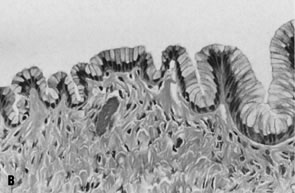

Epithelial cells from mucinous tumors generally resemble endocervical cells (Fig. 11), particularly in benign and low-grade neoplasms. Benign cases are characterized by small, regular fragments of uniform columnar cells with bland, basally located nuclei and vacuolated cytoplasm.82 Desquamated epithelial cells may resemble foamy macrophages.77 Keratin immunohistochemical studies and cytochemical stains for mucin may be useful in distinguishing epithelial cells from macrophages.

Fig. 11. A. Fluid aspirated from a cystic ovarian mass contains cohesive fragments of epithelial cells with small, basally located nuclei without atypia and abundant vacuolated cytoplasm; cytologically, they resemble endocervical cells and are compatible with a mucinous neoplasm (stain, Papanicolaou). B. Corresponding histologic section shows a single, undulating layer of well-organized, endocervical-type glandular epithelium, consistent with mucinous cystadenoma (stain, hematoxylin-eosin).